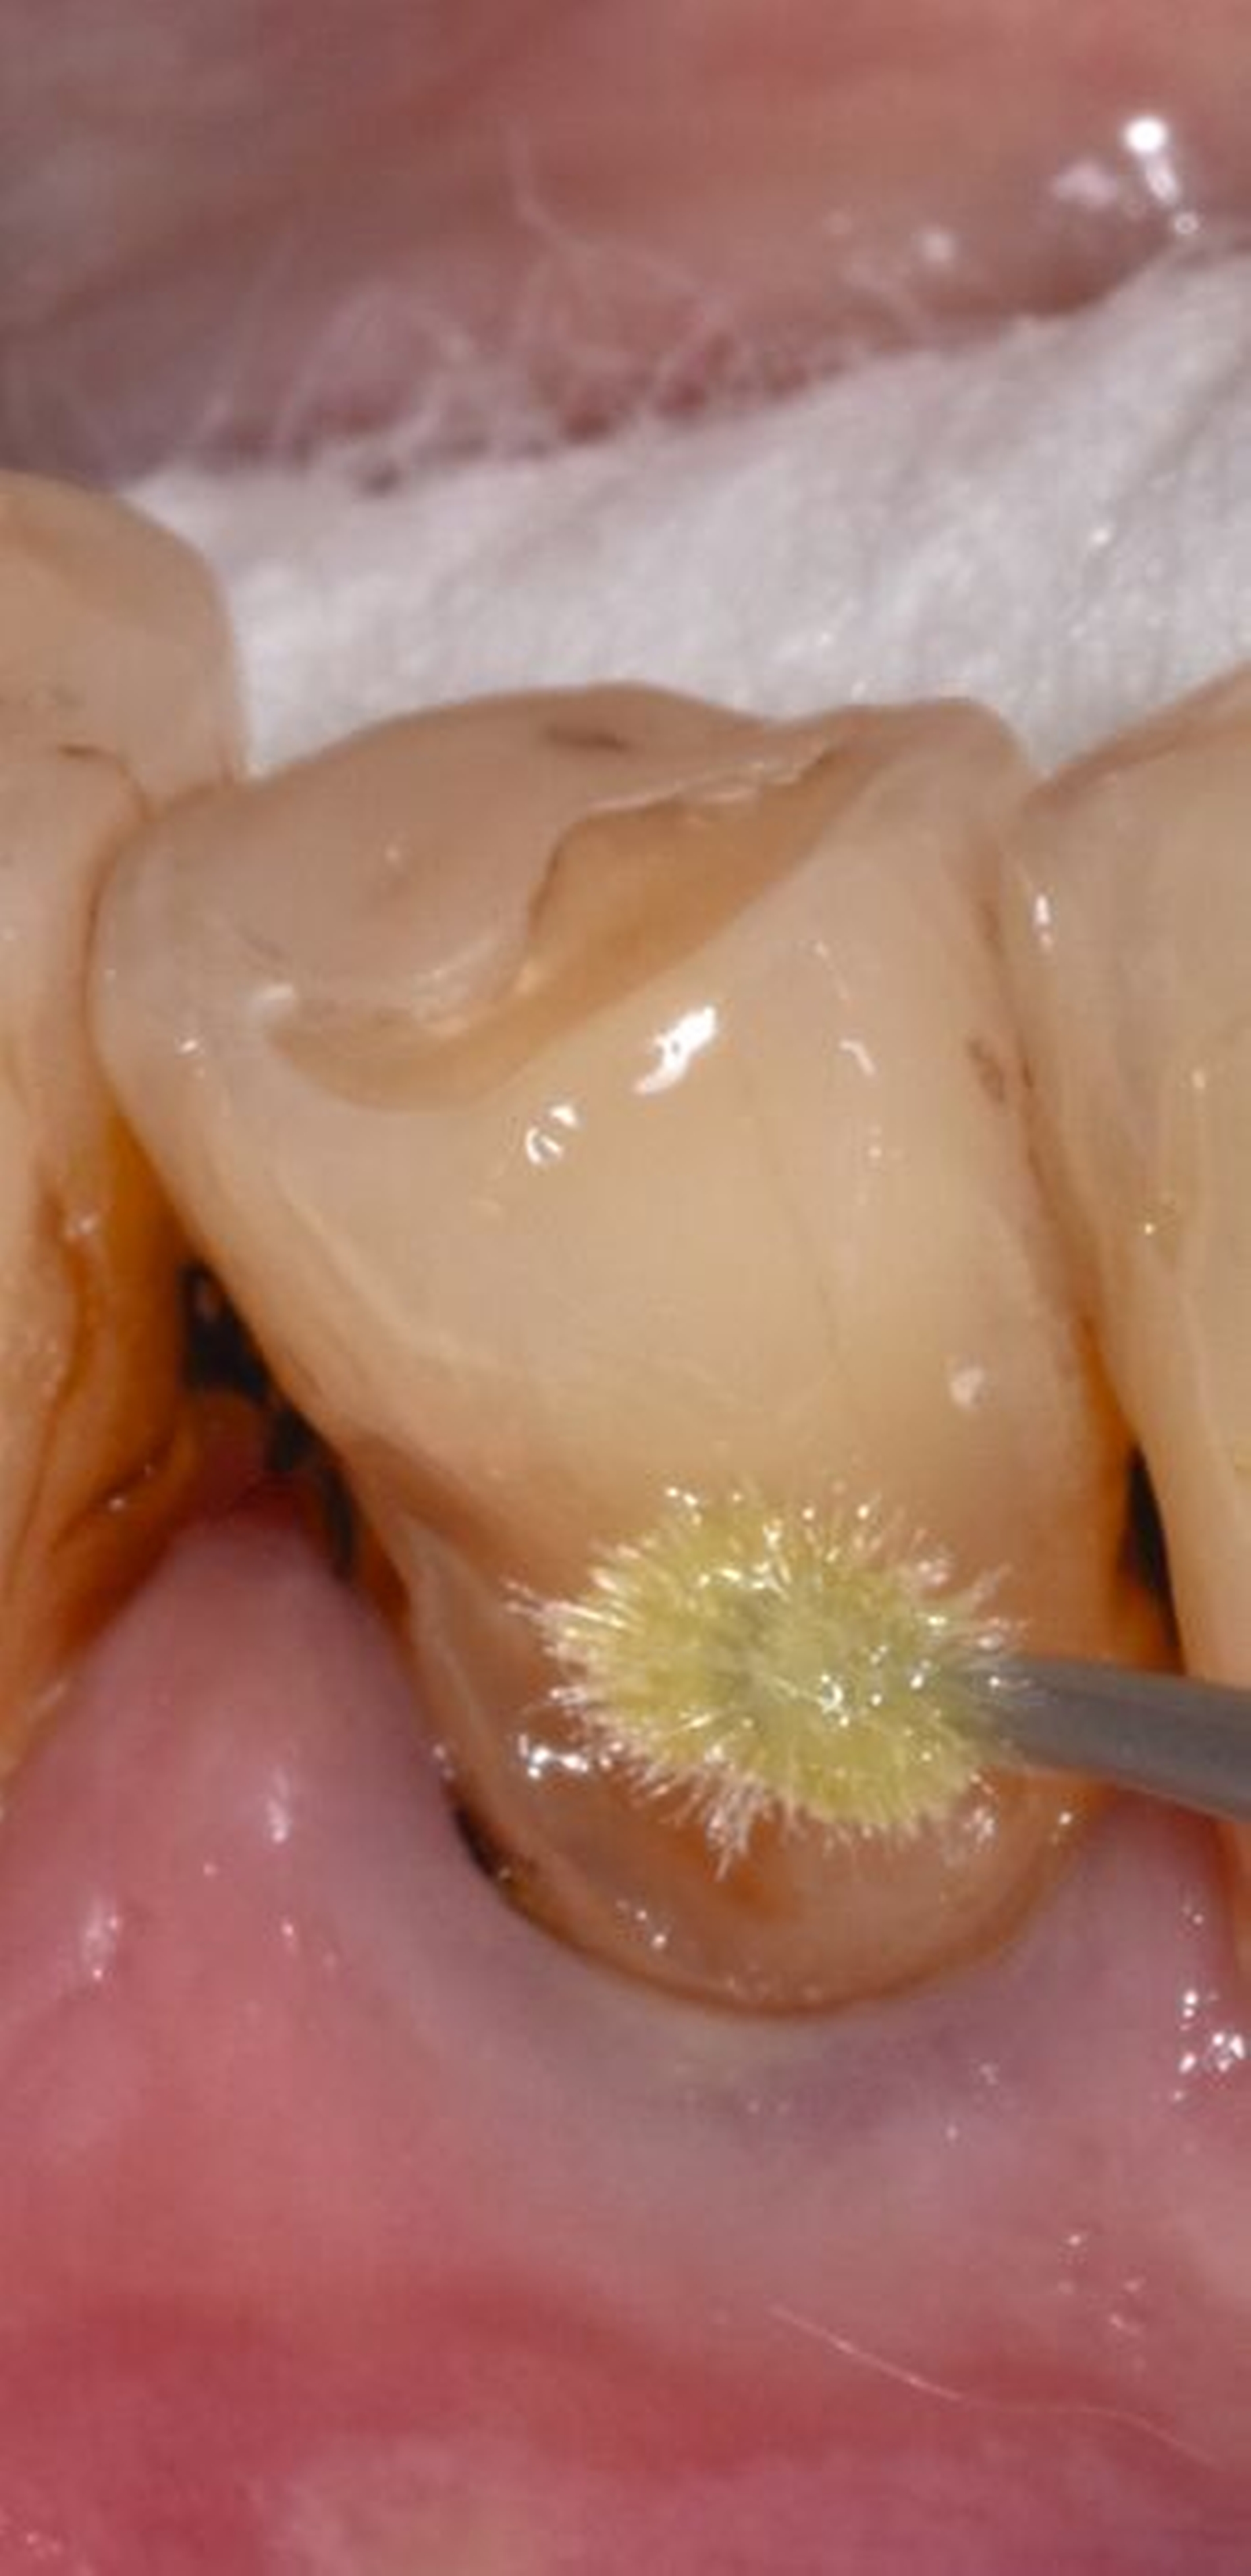

Die anschließende Ausarbeitung und Politur von Kompositrestaurationen ist erforderlich, um die Form der Restauration anatomisch korrekt zu gestalten, Überhänge, die einen Reiz für die umgebenden Weichgewebe darstellen können, zu entfernen und die Oberfläche zu glätten und somit zu vergüten. Polierte Kompositoberflächen sind widerstandsfähiger gegen Alterungs- und Abnutzungsvorgänge in der Mundhöhle. Raue Kompositoberflächen fördern die Plaqueakkumulation (Abbildung 3) und somit die Verfärbungstendenz des Materials. Die Glanzretention ist jedoch limitiert und je nach Ausgangsmaterial und Polierprozess unterschiedlich lang anhaltend.

Die Studienlage zur Politur erwies sich insgesamt als limitiert. Die inkludierten Studien [Jang et al., 2017; Nassar et al., 2014] wiesen zwar methodische Schwächen auf, ließen aber die Formulierung einer konsensbasierten Empfehlung zur Durchführung einer Politur zur Oberflächenvergütung und zur Reduzierung der Plaqueanlagerung zu. In Bezug auf die Auswirkung einer Politur auf das längerfristige Überleben oder Versagen besteht allerdings eine Forschungslücke, so dass dazu keine Aussage gemacht werden konnte.